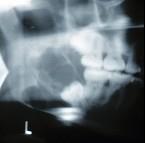

某患者一侧下颌磨牙区、下颌角及升支部渐进性膨大,按之有乒乓球感。X线片(如图)示多房性密度减低影,分房大小相差悬珠,分隔清晰锐利、阴影边缘呈切迹状,阴影内牙根尖有不规则吸收。该病最可能的诊断是 ( )

A.颌骨血管瘤B.成骨肉瘤C.牙源性纤维瘤D.牙源性角化囊肿E.成釉细胞瘤

E